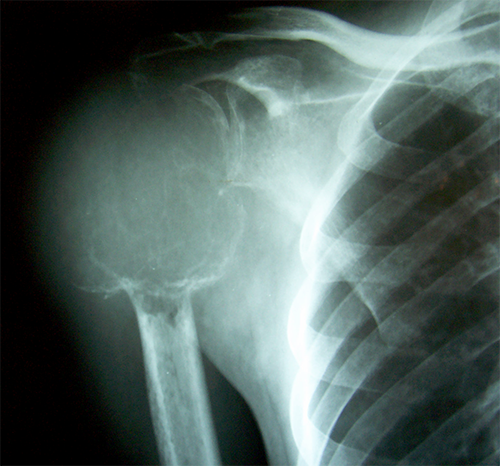

Case:7 GCT Humerus

Spine Surgeon Best In Rajasthan

Pre-Op